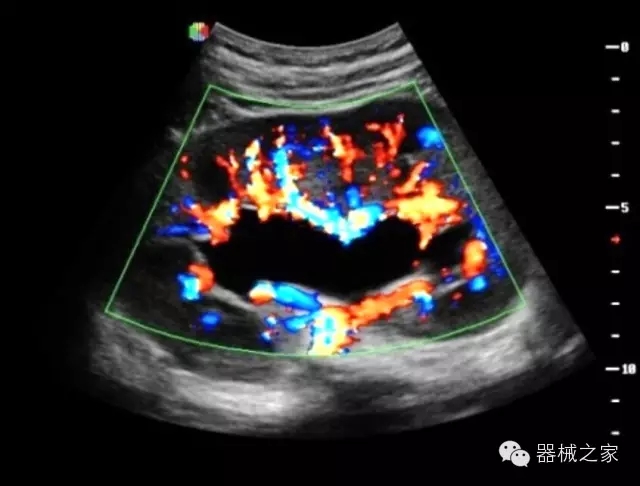

臨床圖片賞析

產(chǎn)品特點(diǎn)

·全球目前唯一一款配備主機(jī)雙探頭接口,整機(jī)重量(含電池)在5公斤以內(nèi)的便攜式彩超;

·一款互聯(lián)網(wǎng)彩超,只要有手機(jī)信號(hào)的地方就可以非常方便地實(shí)現(xiàn)遠(yuǎn)程會(huì)診和病案調(diào)??;

·獨(dú)有的HoloTM PW 實(shí)時(shí)3取樣門PW成像技術(shù),精確進(jìn)行血管診斷;

·一鍵優(yōu)化B、Color、PW,Auto Doppler自動(dòng)識(shí)別血管位置、偏轉(zhuǎn)角度等,提高工作效率;

·30°超廣角精細(xì)偏轉(zhuǎn)成像技術(shù),更優(yōu)異的頻譜圖像;